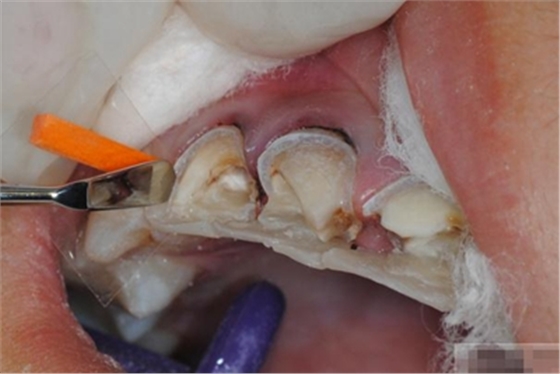

選擇合適的完成鉆制備根管,

通常深入到根管的1/2至2/3處

何種情況應(yīng)該使用纖維樁呢?

是否使用根管纖維樁取決于剩余牙體組織的強(qiáng)度,這主要決定于剩余邊緣嵴的數(shù)量。

a 兩側(cè)邊緣嵴均完整,無需使用根管纖維樁。

b 一側(cè)邊緣嵴缺如:評(píng)估牙體缺損情況??沽π陀幸蓱]則加用根管纖維樁。

c 兩側(cè)邊緣嵴均缺如,必須使用根管纖維樁。

在使用根管纖維樁時(shí)根管預(yù)備的深度應(yīng)該是多少呢?

在回答這個(gè)問題前,首先應(yīng)該了解根管內(nèi)的粘接狀況。最佳的粘接效果發(fā)生于根管的冠1/3和中1/3。由于根1/3的牙本質(zhì)小管往往不能充分敞開,此區(qū)域幾乎沒有粘接作用發(fā)生,所以,根管纖維樁放置的深度無需超過根中1/3。同樣重要的是,根管預(yù)備時(shí)鉆的速度不要過快,防止飛濺的牙膠粘在根管內(nèi)壁上。所以,根管壁的清理也很重要,以確保牙本質(zhì)小管充分開放。Dr.Vanini使用噴砂和酸蝕來充分清理根管壁和窩洞。研究顯示,粘接劑的作用也很重要,粘接根管纖維樁要求使用滲透力強(qiáng)粘結(jié)作用好的粘接劑。

【纖維樁制作】

修整纖維樁長度

取出纖維樁,按所需長度裁截纖維樁 在有水條件下 用切割砂片或車針截取纖維樁,切勿使用鉗子,剪刀或鑷子以免破壞樁的結(jié)構(gòu)